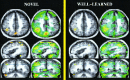

The level of familiarity of a given stimulus plays an important role in memory processing. Indeed, the novelty/familiarity of learned material has been proven to affect the pattern of activations during recognition memory tasks. We used visually presented words to investigate the neural basis of recognition memory for relatively novel and familiar stimuli in schizophrenia. Subjects were 34 healthy volunteers and 19 schizophrenia spectrum patients. Two experimental cognitive conditions were used: 1 week and again 1 day prior to the PET imaging subjects had to thoroughly learn a list of 18 words (well-learned memory). Subjects were also asked to learn another set of 18 words presented 1 min before the PET experiment (novel memory). During the PET session, subjects had to recognize the list of 18 words among 22 new (distractor) words. Subjects also performed a control task (reading words). A nonparametric randomization test and a statistical t-mapping method were used to determine between- and within-group differences. In patients the recognition of novel material produced relatively less flow in several frontal areas, superior temporal gyrus, insular cortex, and parahippocampal areas, and relatively higher activity in parietal areas, visual cortex, and cerebellum, compared to controls. No significant differences in flow were seen when comparing well-learned memory activations between groups. These results suggest that different neural pathways are engaged during novel recognition memory in patients with schizophrenia compared to healthy individuals. During recognition of novel material, patients failed to activate frontal/limbic regions, recruiting a set of posterior perceptual brain regions instead.